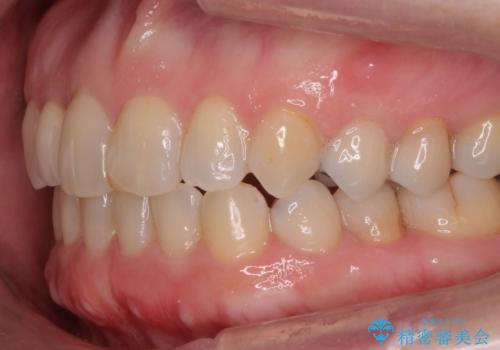

- 右上の2番目の前歯がとがった形をしていたため、セラミックで形を整えています。

短くてとがった歯の形が反対側と同じ形となり、左右対称となり、ずいぶん自然な印象になりました。

下の前歯とのかみ合わせが切端咬合だったため、前歯の部分矯正も併せて行っています。(費用別途)